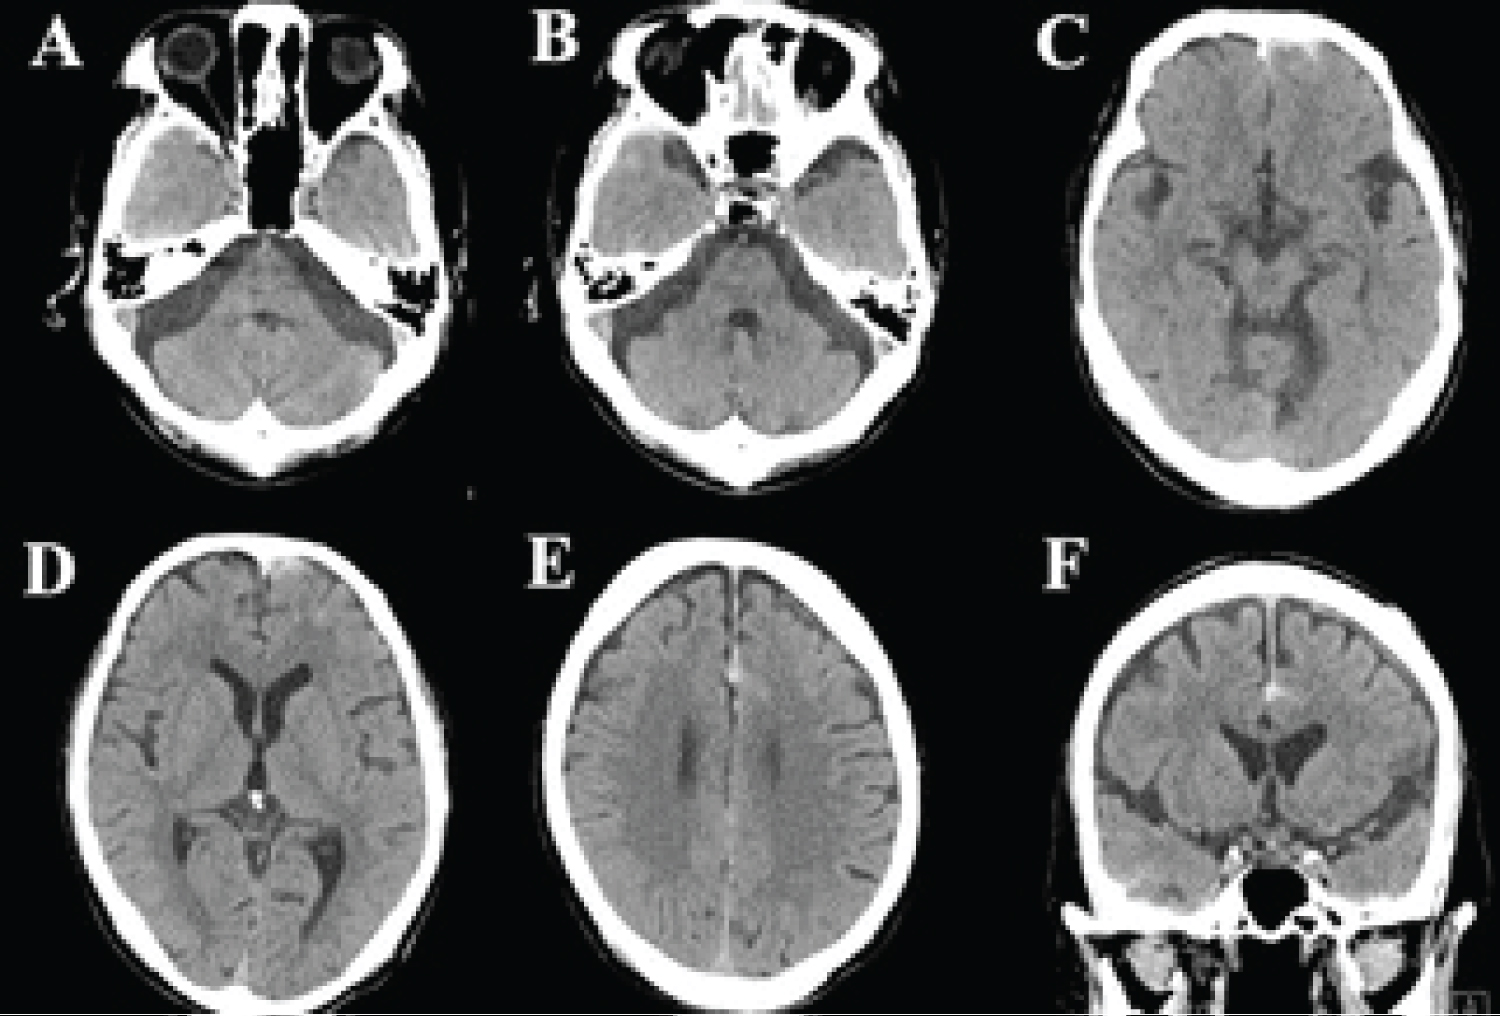

CT scans taken just 45 min after the head injury showed contusion or traumatic subarachnoid hemorrhage (SAH) in the right temporal tip, the left frontal tip (Figure 3A, Figure 3B, Figure 3C and Figure 3D), and SAH in the anterior interhemispheric space around the pericallosal artery (Figure 3E and Figure 3F). We had told the family that the patient could be discharged within a few weeks (possibly on foot) but that there was a very small possibility that the contusion hematomas might expand and hematoma evacuation would then be necessary; repeated CT would be taken 6 hr later regardless the patient's conscious level.

Figure 3: (A-D) CT scan at 45 min after the high-energy injury demonstrating contusions or traumatic subarachnoid hemorrhage (SAH) in the right temporal tip; (E,F) SAH in the anterior interhemispheric space around the pericallosal artery. View Figure 3